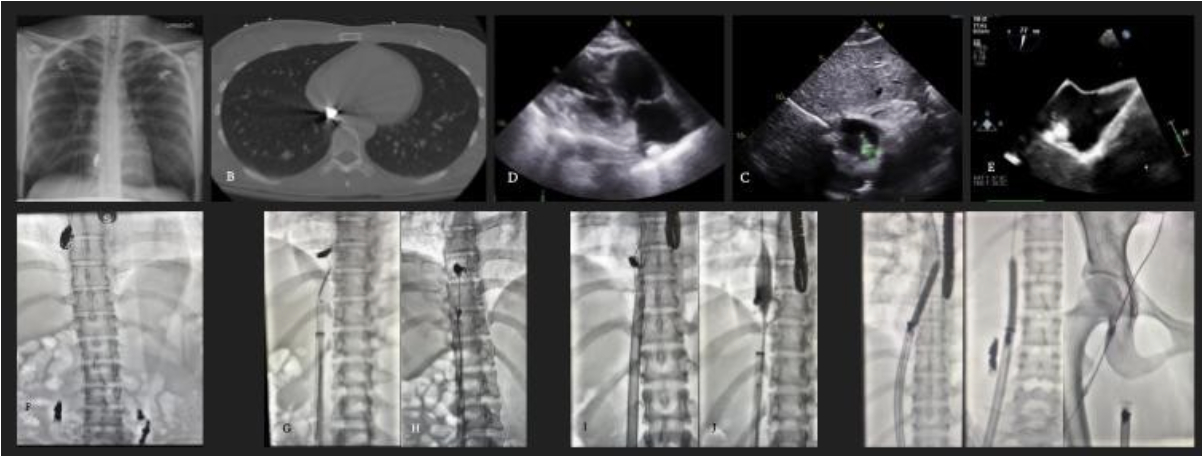

Imaging-Guided Retrieval of a Migrated Coil from the Right Atrium: A Multimodal Endovascular Approach

A 27-year-old female presented with pleuritic chest pain, dizziness, and a history of prior gonadal vein embolization. Imaging revealed a metallic foreign body in the right atrium. Transthoracic echocardiography (TTE) and CT confirmed coil presence (2.25 × 1.25 cm) affixed to the RA roof. Multidisciplinary decision-making favored a percutaneous approach. Preprocedural TEE was performed for localization. Retrieval attempts included use of multi-loop snares, J-wire looping, balloon trapping (Cordis balloon), and ultimately AngioVac aspiration with ECMO backup. An Amplatz Super Stiff wire facilitated device support.

Initial snare attempts led to fraying and partial coil removal. Sequential strategies including balloon trapping via right internal jugular access and mechanical aspiration with AngioVac were employed. A 7 × 20 mm balloon was inflated within the AngioVac sheath at 23 atm to trap the coil. Successful en bloc removal was achieved under fluoroscopy and confirmed by intraoperative TEE. The patient remained hemodynamically stable and was discharged the following day without complications.